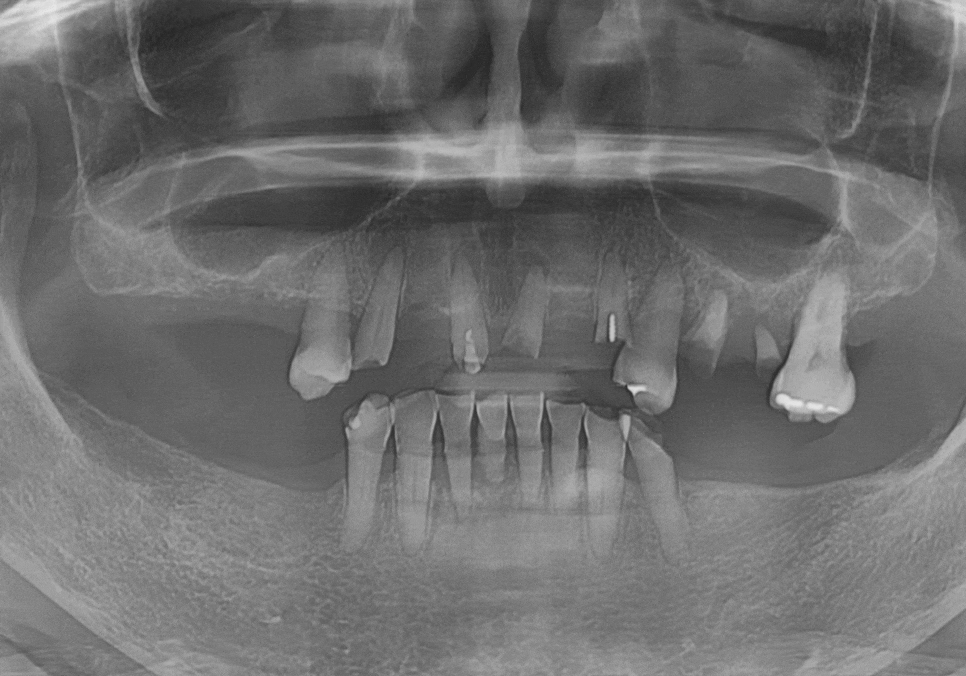

아래턱은 양쪽 어금니를

상실한 지 오래되셨고,

위턱은 대부분의 치아가

뿌리만 겨우 매달려 있었습니다.

파노라마와 CT를 통해 살펴보니

뿌리 끝에 염증이 가득 잡혀 있었죠.